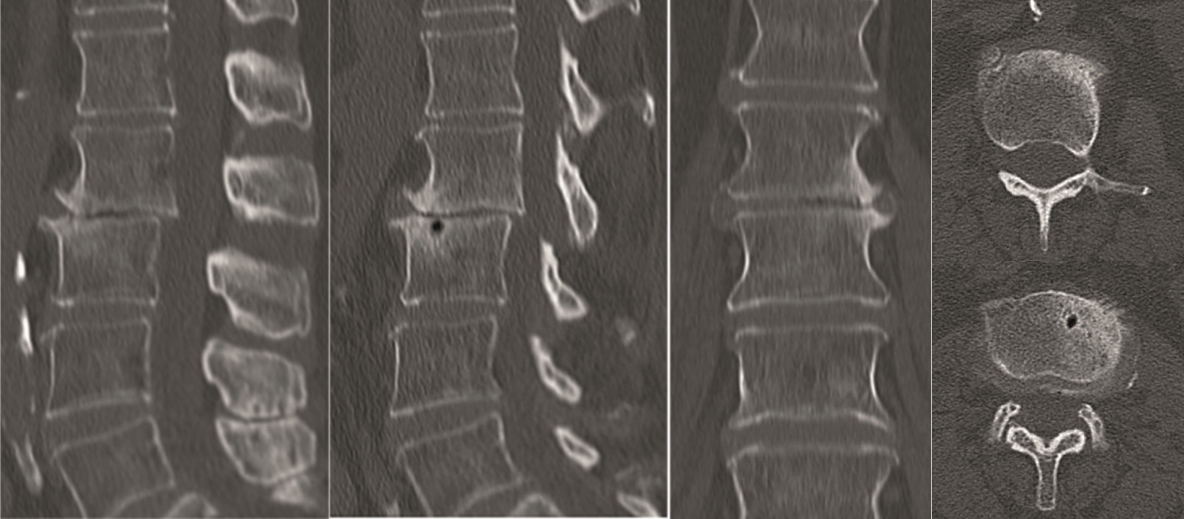

Case 4 : ALIF L4-L5 non union

A 40-year-old man 5 years after ALIF L4-L5 using SynFix with axial low back pain. The CT scan shows locked pseudarthrosis (Fig 17). Nonoperative treatment failed. The treatment option was bilateral Facet Wedge at L4-L5.

A less invasive approach was used with Insight Retractor using the bilateral Facet Wedge. No bone graft. X-ray follow-up after 3 months and CT assessment after 6 months (Fig 18-19).